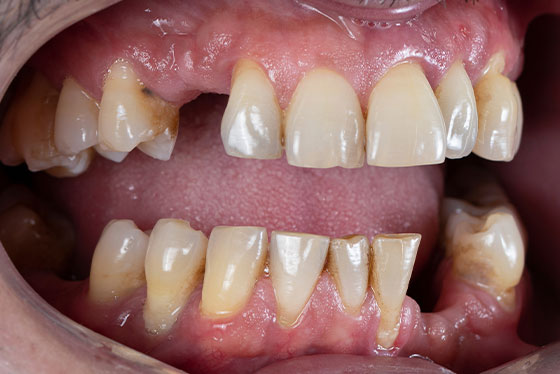

虫歯や歯周病で多くの歯を失ってしまうと、毎日の生活の中で、さまざまなつらさを抱えやすくなります。

「もう一生、美味しく食事を楽しめないのでは…」

「人前で口を開けるのが恥ずかしくて、笑えない」

「言葉がうまく発音できず、会話が苦痛になってきた」

このようなお悩みが続くと、外出や人付き合いを避けるようになったり、性格まで変わってしまったと感じる方もいらっしゃいます。

総入れ歯に変えたものの、お悩みがなかなか解決しない…という声も多く聞かれます。